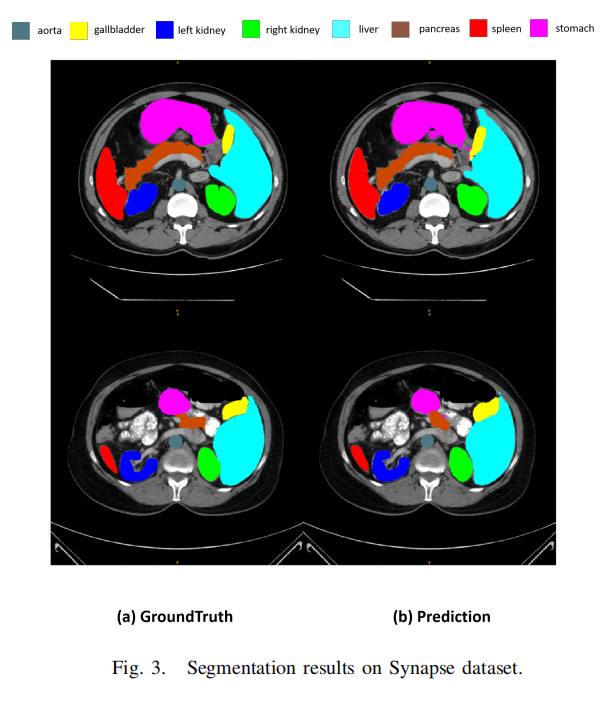

本文使用Synapse数据集进行评估,这是MICCAI 2015多图谱腹部标记挑战的一个公开可用的多器官分割数据集。它包括30个腹部CT扫描。根据之前的工作,总共使用18个案例进行训练,12个案例用于测试。本文以Dice相似系数(DSC)和95% Hausdorff距离(HD95)的指标报告在8个腹部器官(即主动脉、胆囊、脾脏、左肾、右肾、肝脏、胰腺、胃)上的结果。

图3展示了一些分割结果。然而,集成CNN编码器和可学习权重参数的设计可以进行修改,以分析和评估所提出方法的性能。本文相信利用Transformer或其他有效的网络设计将会获得更高的性能。在未来,本文将探索更先进的设计选择,以达到最佳结果。